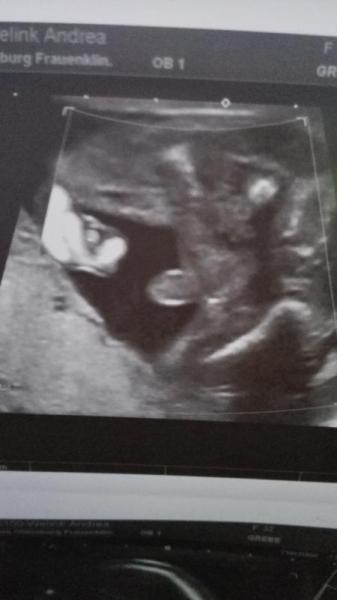

Na,wer so eindeutig zeigt,was er hat,der darf auch blaue Sachen tragen *lol*... Mein Großer zeigte es so kurz vor der Geburt (gewusst haben wir es schon in der 12.SSW):

Bild zu

Würde einen Jungen auch kein Rosa anziehen. Außer vielleicht Boddys oder im Garten das UV Schutz T-shirt. Und Glückwunsch zu Sohne Mann.